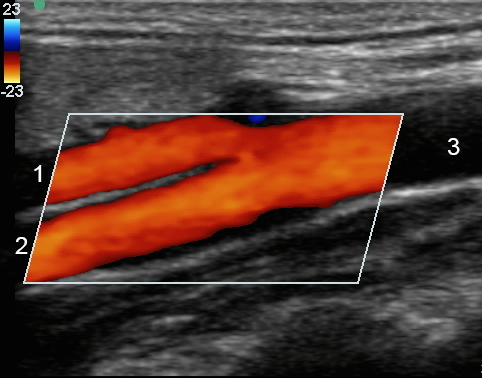

色と総頸動脈分岐部

外部頸動脈 (ECA)

内頸動脈 (ICA)

総頸動脈(CCA)